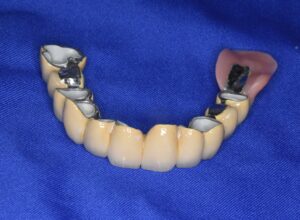

ケース2:上下に多くの問題があった70代後半男性

この方は虫歯や歯周病で残存歯が少なく、グラグラの歯が多い状態でした。最初は保険のクラスプ義歯を入れていたものの安定せず、硬いものを噛めないため外していることが多かったそうです。外見を重視してナイロン義歯を試されましたが、期待したような咬合回復は得られず、全体の再治療を希望して来院されました。

まず全顎の虫歯と歯周病の治療を行い、上顎は残存歯すべてに内冠をかぶせて連結し、全体を支えるテレスコープ義歯を製作しました。装着後は「入れ歯」というよりは取り外し可能な長いブリッジの感覚で、違和感がほとんどないとのことです。

このケースは「残った歯をチーム化して守る」発想が有効であった例です。